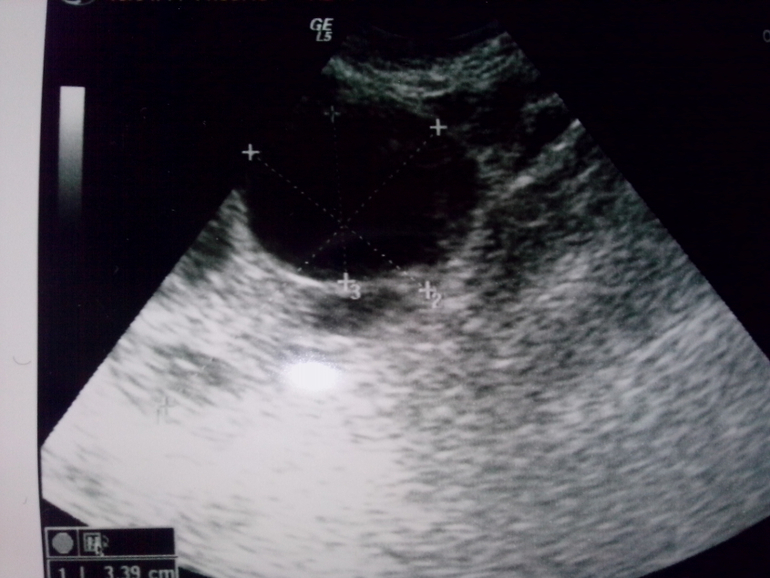

В итоге: эндометрий 12,2 (у меня в первой фазе выше 9 не бывает) в ПЯ нет ничего, мелкие фолики, а в ЛЯ - ДФ 17!!! Девочки, он ПРОСНУЛСЯ!  У меня только там труба осталась! Я аж там попрыгала от счастья

Я двести раз переспросила, может это ЖТ? А она НЕТ 100%. К слову, у этого узиста была в первый раз. График, фото ЛЯ:

Я так понимаю когда полость не полностью черная а частично серое, как у меня на фотке сверху, то это не фоликул. Я еще на мониторе присматривалась к нему и в некоторых проекциях этой серой массы было оч много. Сейчас попробую вам ссылку найти ту с примерами

Я так понимаю когда полость не полностью черная а частично серое, как у меня на фотке сверху, то это не фоликул. Я еще на мониторе присматривалась к нему и в некоторых проекциях этой серой массы было оч много. Сейчас попробую вам ссылку найти ту с примерами